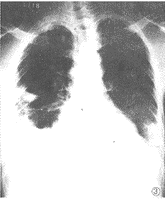

其他輔助檢查:X線表現無特異性,包括斑片影的支氣管肺炎和大葉浸潤,常見於下葉或右中葉,約20%病例伴有胸腔積液。